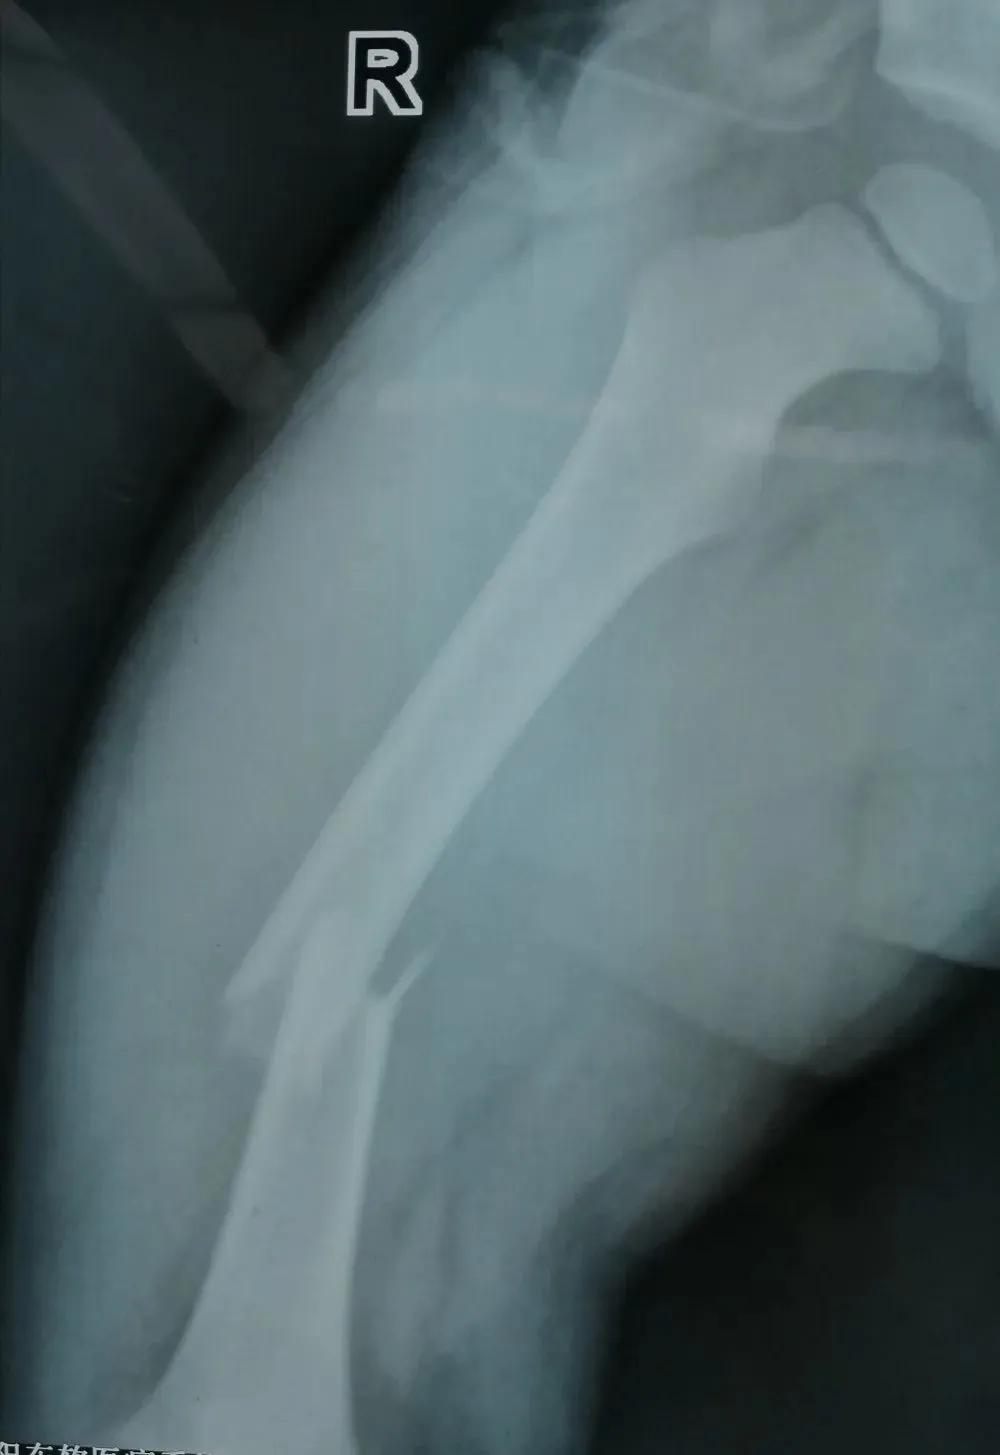

近日景谷县人民医院外二科收住两名患儿,其中一名:李xx,7岁,因摔伤左小腿后疼痛、活动受限3小时收入,入院后完善相关检查,明确诊断为左胫骨中下段螺旋性骨折。另一名患儿:胡xx,3岁,因摔伤右大腿后疼痛、活动受限8小时收入,入院后完善相关检查,明确诊断为右股骨中段骨折。

景谷县人民医院骨科接诊两位患者后,分别结合患儿的年龄、相关检查资料做了综合评估、讨论,征得家属同意后,精心制定了手术方案,为两名患儿成功完成了弹性髓内钉的微创治疗。